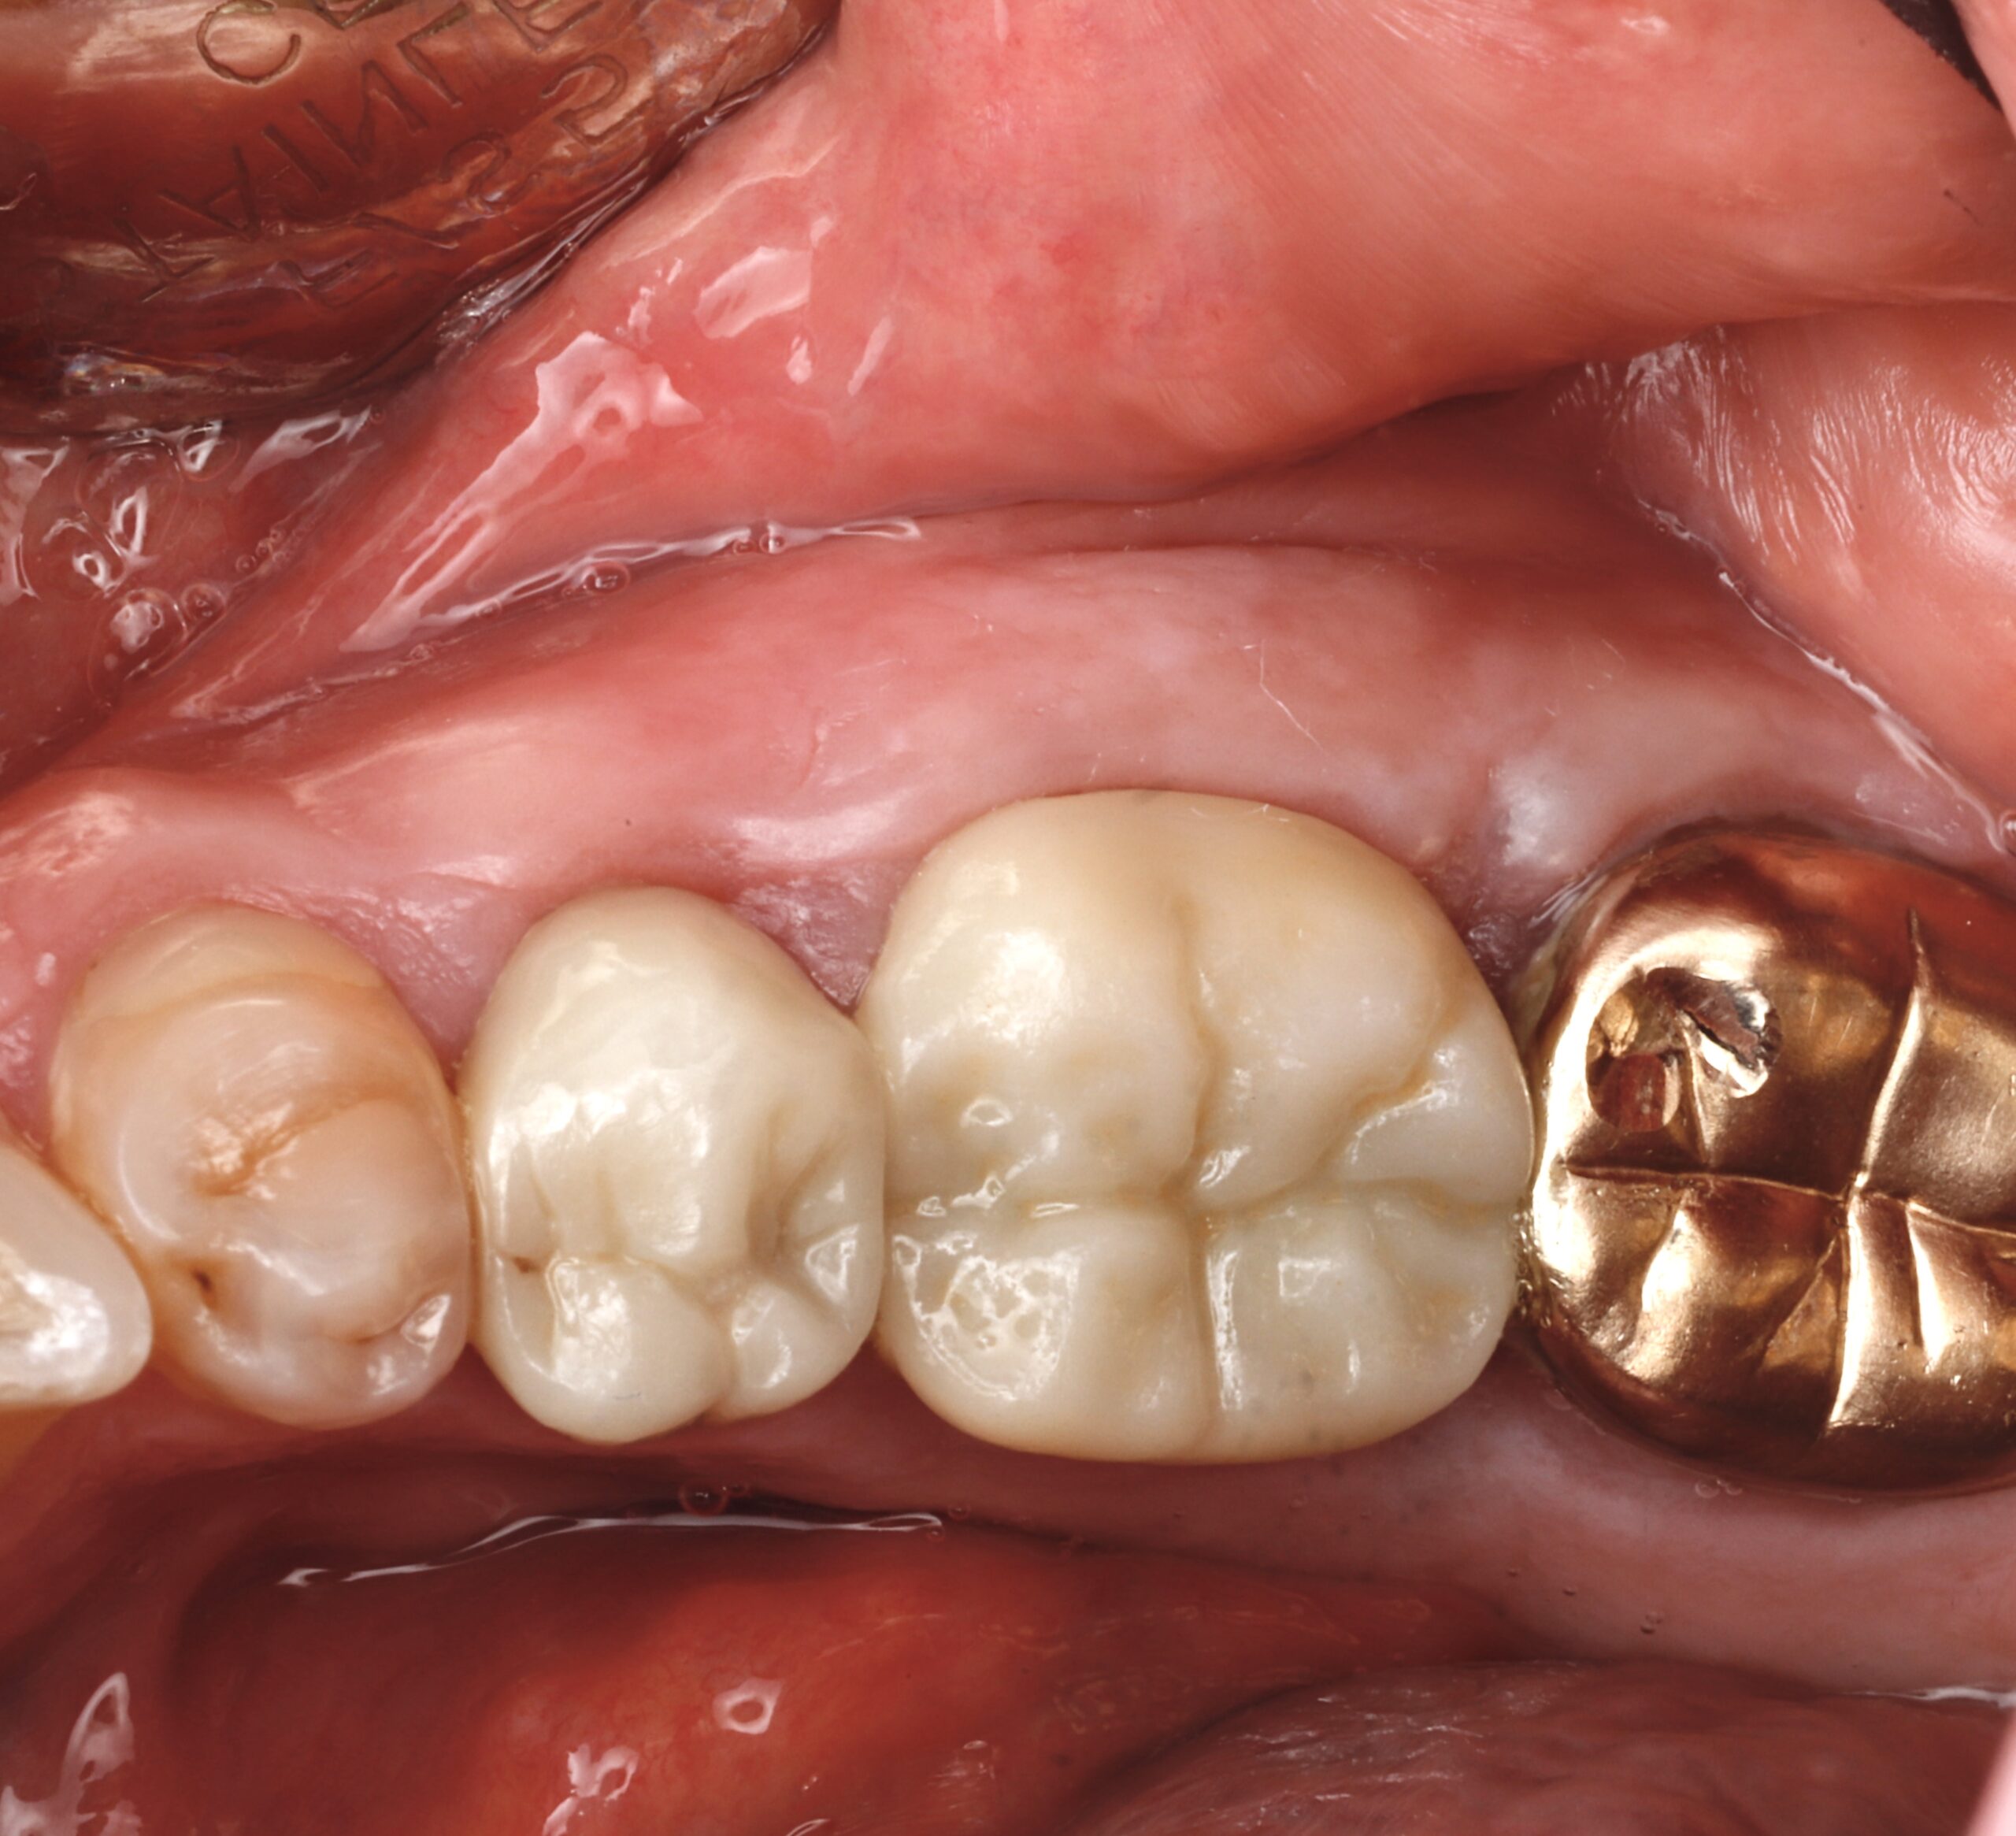

For most people, the inside of the mouth feels smooth and consistent. But some patients develop extra bony growths—called tori—along the roof of the mouth (palatal tori), the inside of the lower jaw (mandibular tori), or other areas. While tori aren’t dangerous, they can become a frustrating obstacle in daily life.

Tori are harmless, noncancerous bone growths that form in the mouth. They can vary in size, shape, and location. Some remain small and unnoticed for years, while others grow large enough to cause problems.